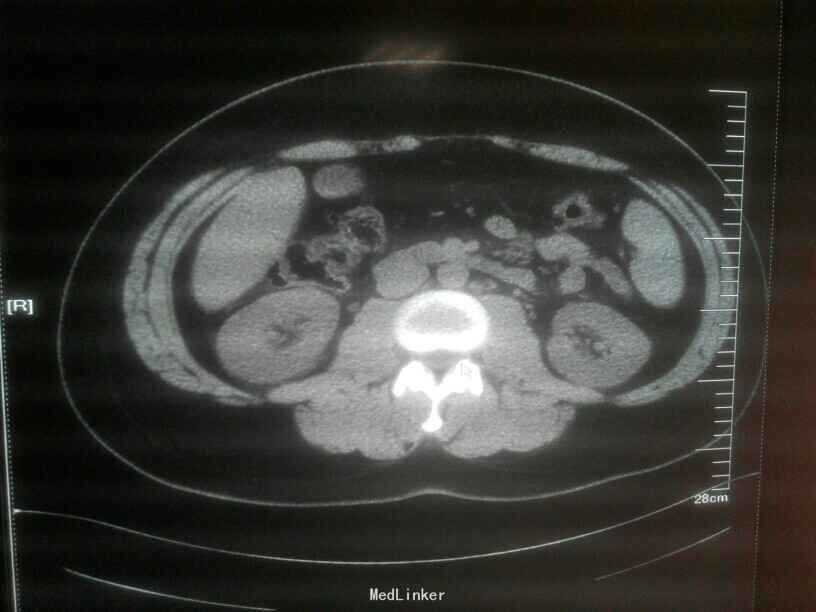

辅助检查:血常规,白细胞:4.99×109/L,中性粒细胞,4.23×109/L;血糖10.57mmol/L;白蛋白33.9g/L;腹部CT:右下腹髂窝渗出并局部肠管扩张积液、考虑阑尾炎可能性大,病理:(阑尾)急性化脓性阑尾炎伴周围炎,部分坏疽;

诊断:急性阑尾炎、急性化脓性腹膜炎、肠梗阻

急性阑尾炎是最常见的外科急腹症,本病例病程典型,阑尾坏疽,炎性渗出致肠管扩张而导致腹平肠梗阻表现。